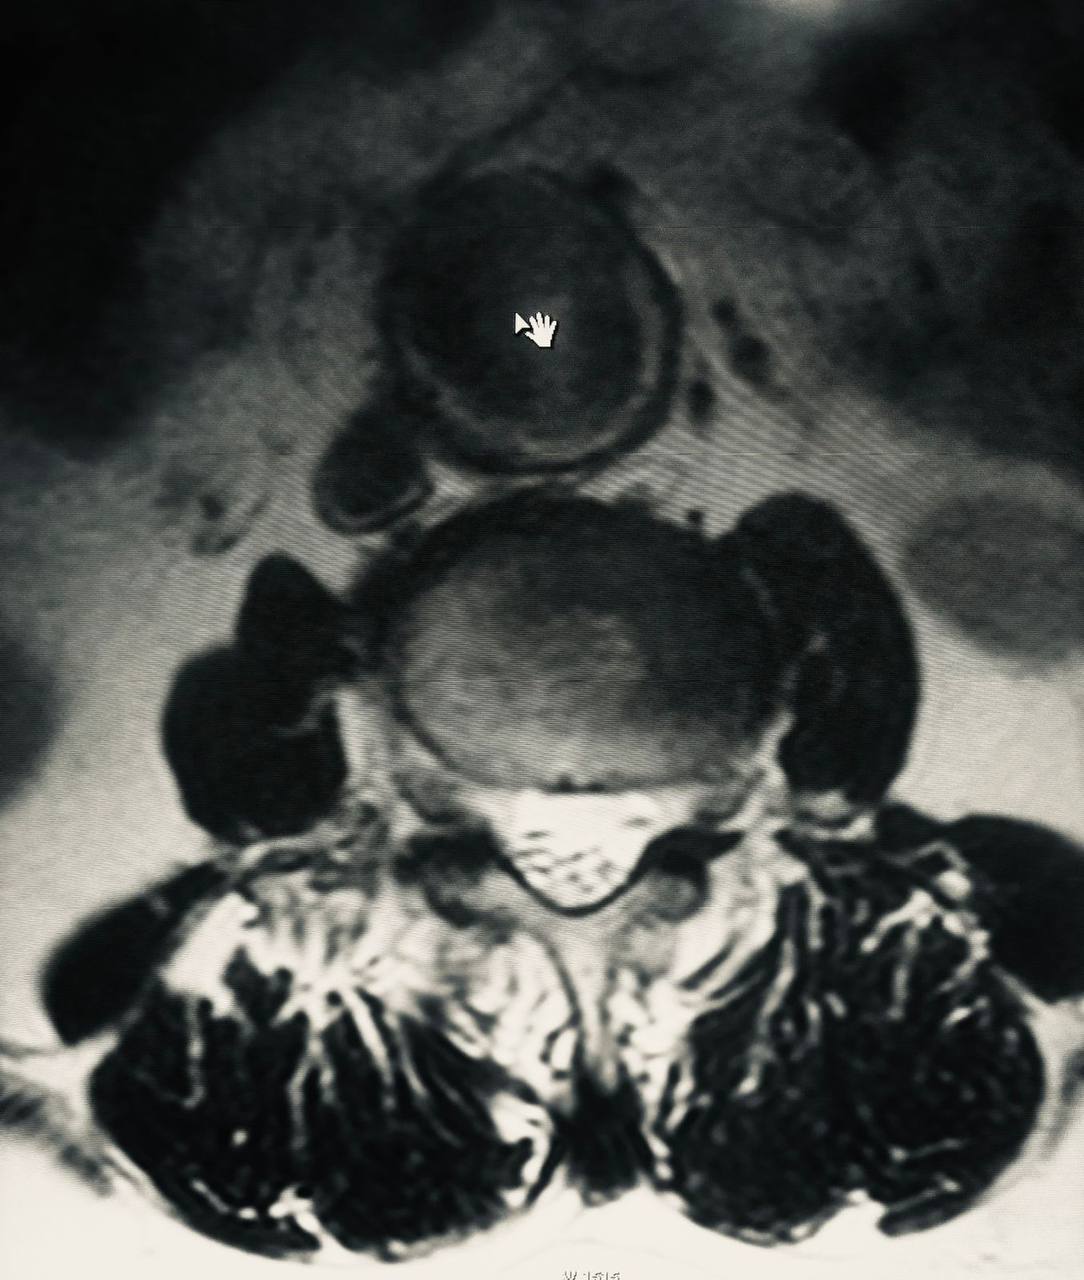

На прием обратился пациент (74 года) с жалобами на боли в спине. Для диагностики провели МРТ пояснично-крестцового отдела позвоночника, на котором и выявили крупную аневризму брюшного отдела аорты.

В анамнезе у пациента стентирование коронарных артерий и аортокоронарное шунтирование. Про аневризму брюшного отдела аорты он не знал, так как протекала бессимптомно.

Пациенту порекомендовали КТ с контрастированием для дообследования и консультацию сосудистого хирурга. Желаем здоровья и уверены, что такая «находка» поможет принять своевременные меры для его сохранения.